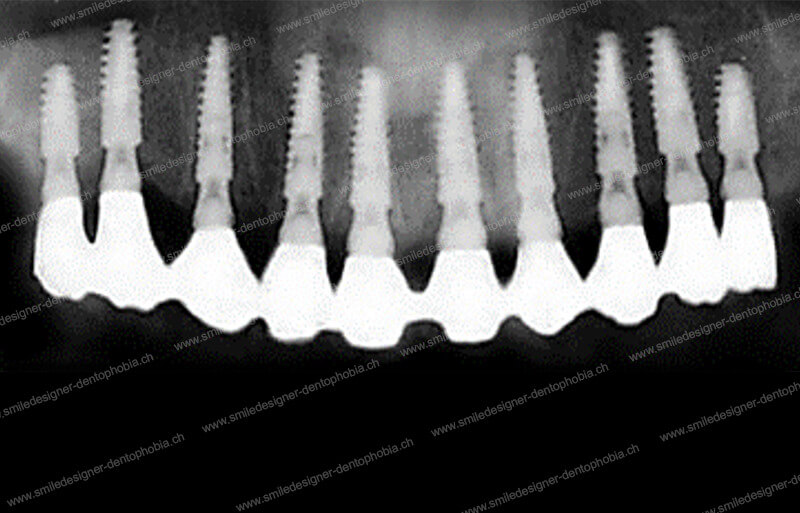

Cas clinique « GOLD STANDARD MCI » bi-maxillaire : Bridge implanto-porté sans extension postérieure (ALL ON 10). Version définitive des bridges avec un cosmétique en céramique.